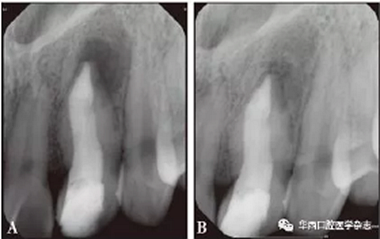

A:術(shù)后3個(gè)月;B:術(shù)后1年。

圖 4 術(shù)后根尖片

根尖屏障術(shù)后1年(2018年3月21日)復(fù)診攝X線片,患牙根尖區(qū)低密度透射影像明顯縮小,根尖區(qū)趨于愈合(圖4B)。